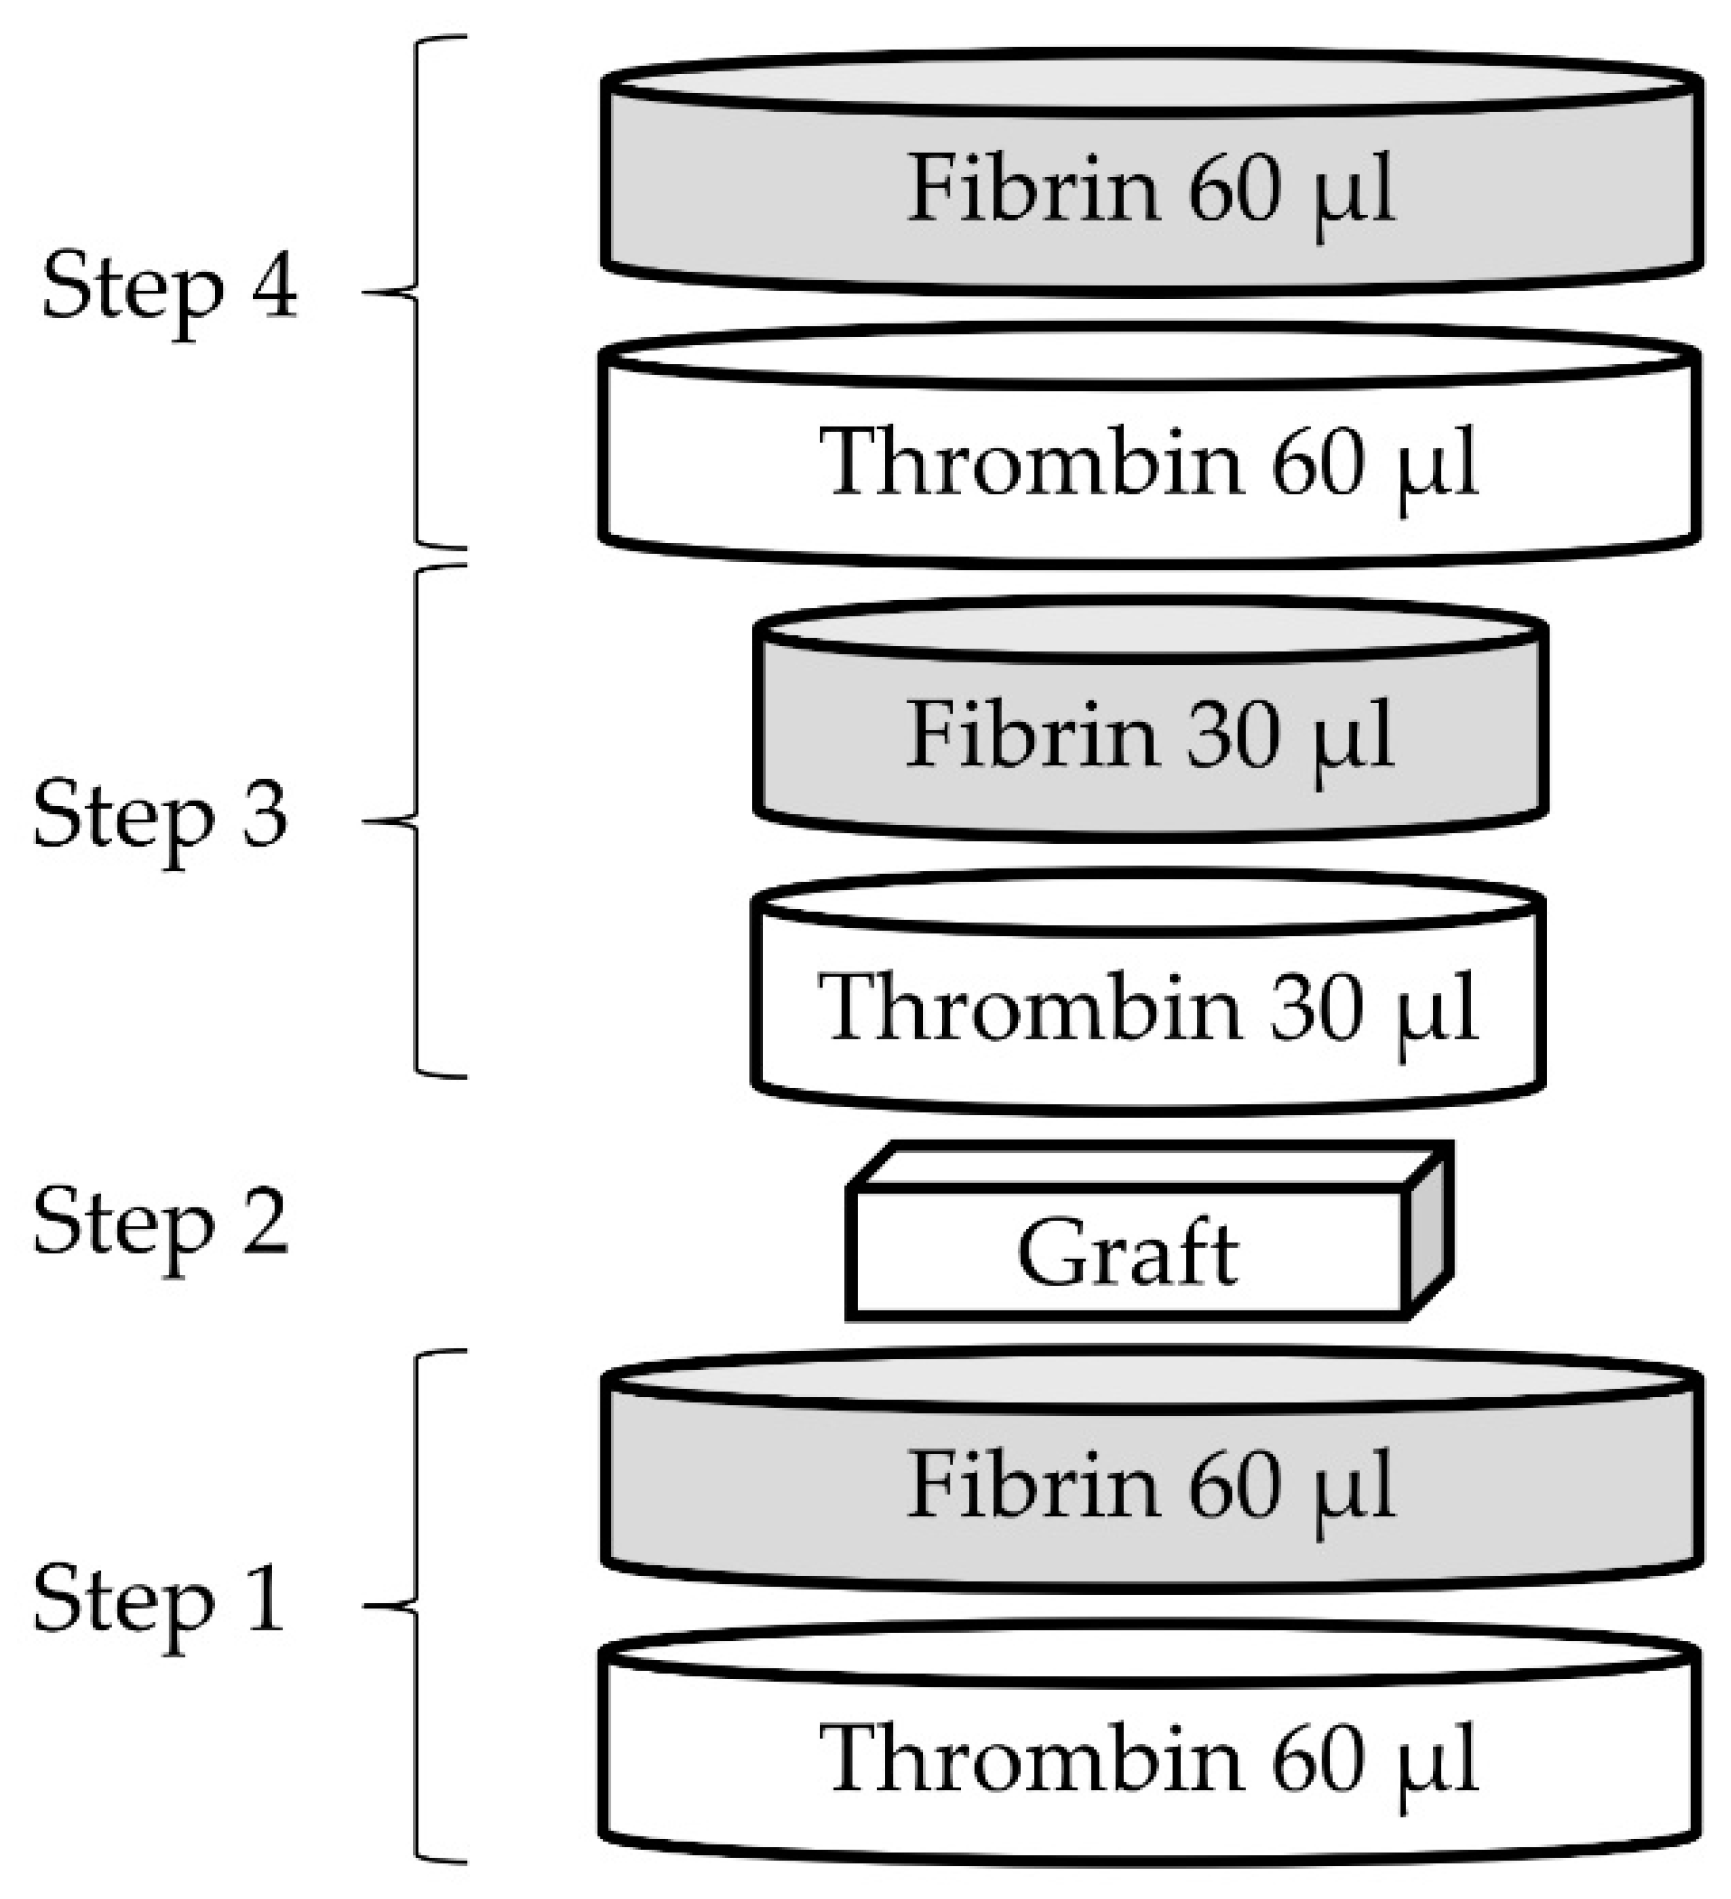

4.1.5. Fibrin Glue

4.2.3. Preparation of Coated Samples